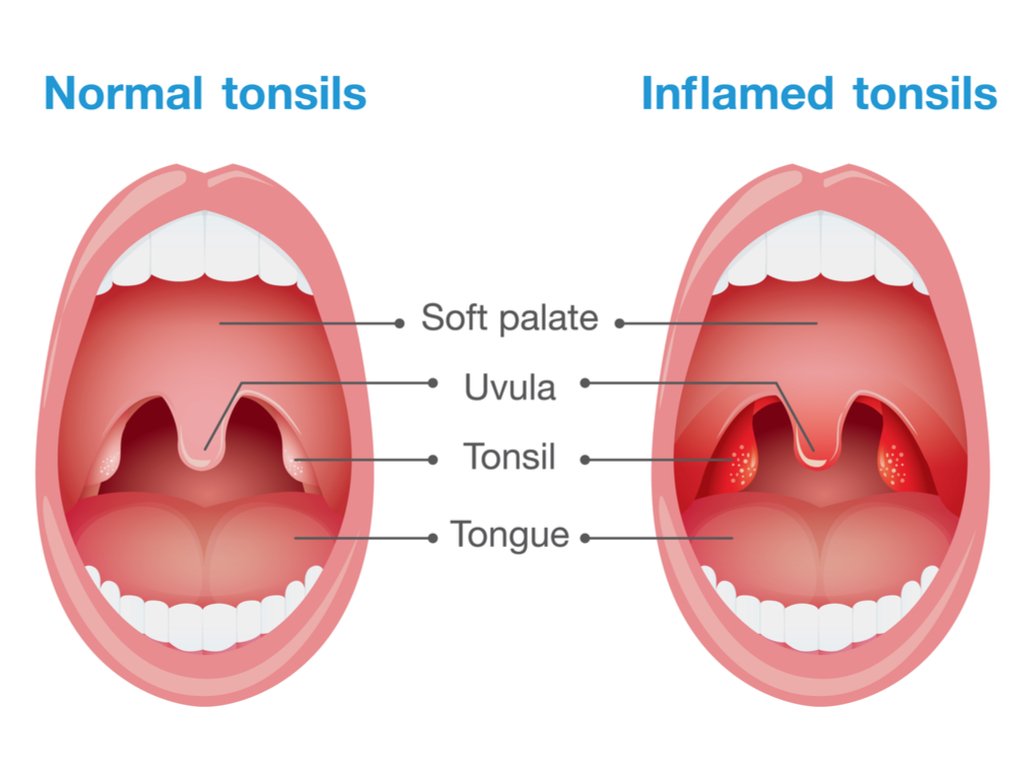

البعض يعاني رائحة الفم الكريهة "Halitosis" لاسباب متعددة ، نستعرض بعض هالاسباب و طرق الوقاية و العلاج مع بعض بهالثريد: